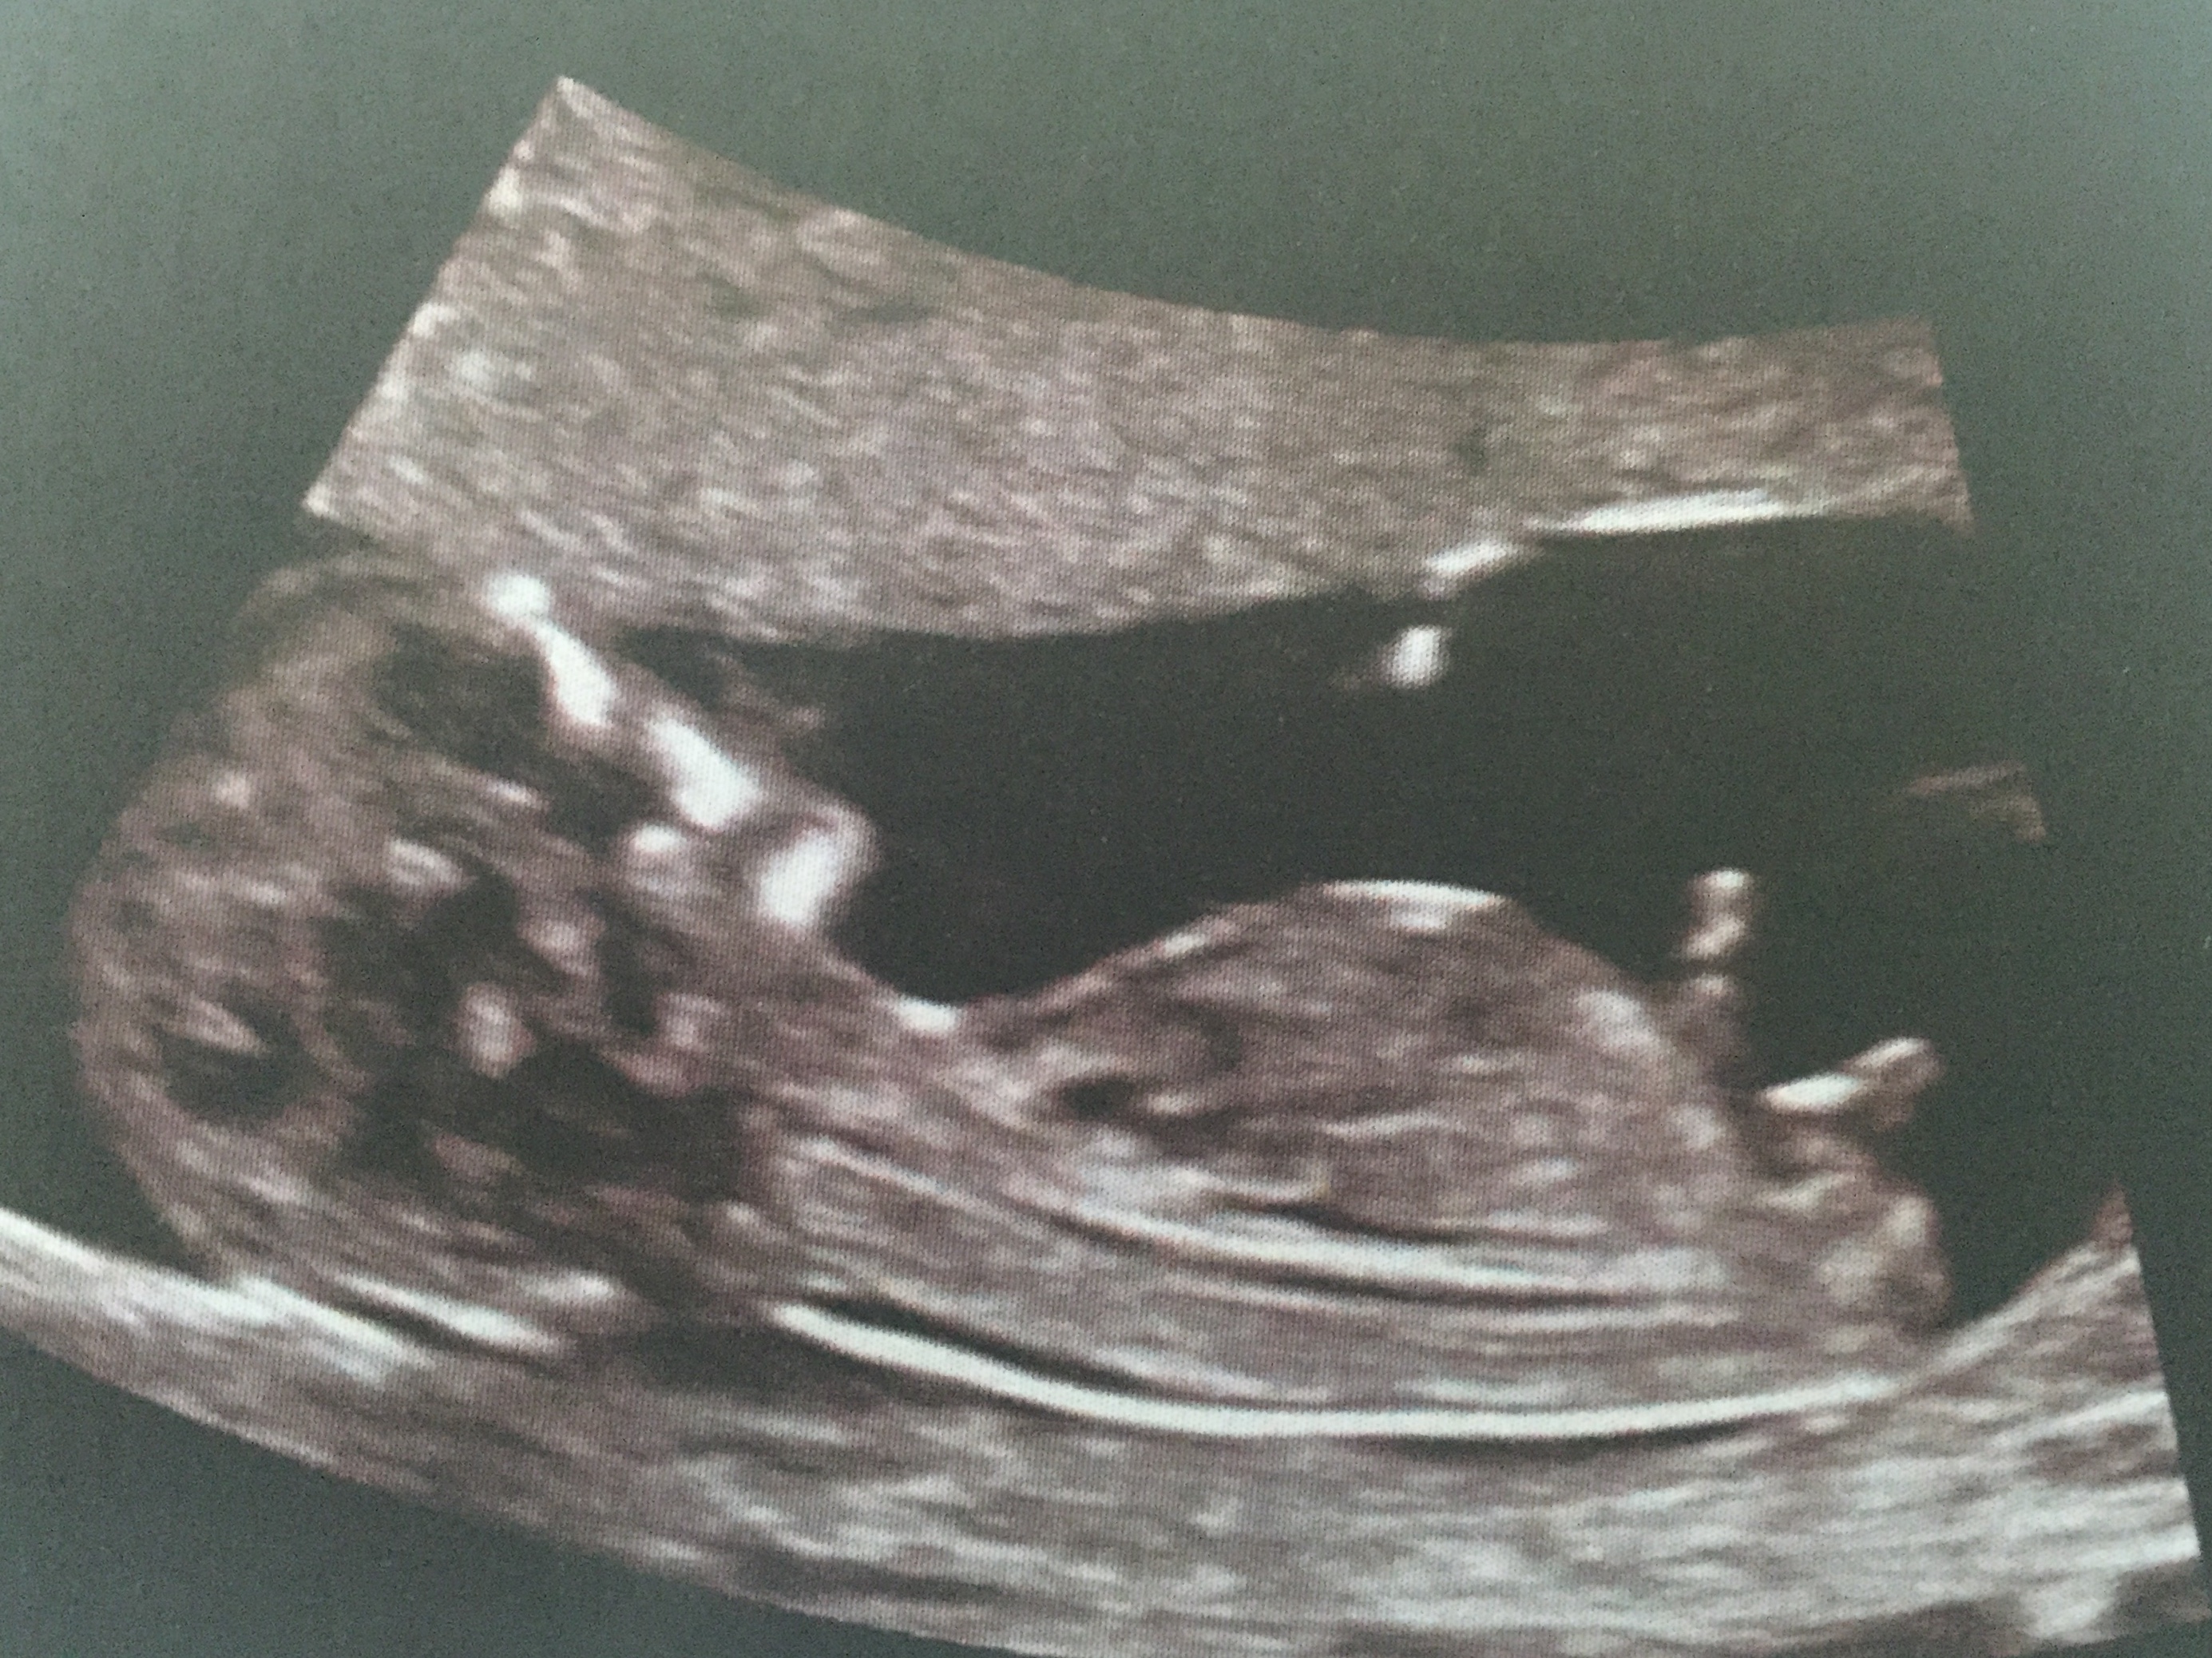

Twin 2

Twin a a boy and twin b looks girly but maybe the whole nub isn't imaged. At least 1 boy

i have a another pic of twin 2 if that helps

Attachment 24124

I almost thought B/G but the two new ones almost make me think B/B The last one is not reliable because bubs is turning away

Tech said twin 1 was a boy and couldnt call twin 2!

yeah its a toughy. 2 in the first looks girly as all get out but that last set it looks like a ski slope for boy.

B/B guess for me congrats on twinnies X

Boy, boy guess too :)

B/B lean from me. Congrats on your twins!

2 boys for me as well, congratulations!!!